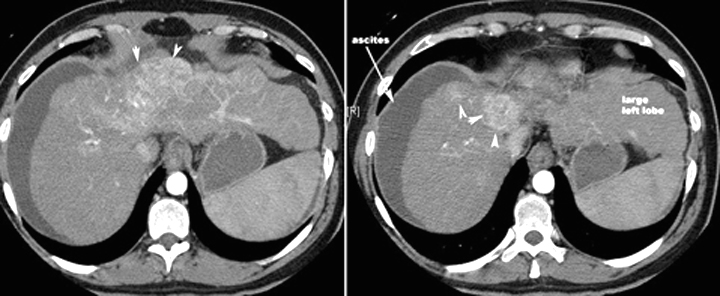

CT scan in a patient with Multicentric hepatoma

CT scan in another patient with Hepatoma

Arrowheads point to the enhancing mass. Note the lobulated margins of the liver, lower density than spleen and ascites indicating underlying cirrhosis.